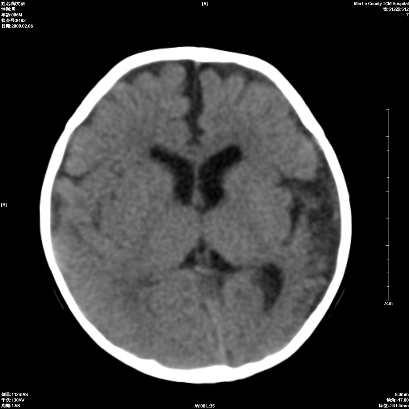

以下是引用wxq2008在2009-2-6 17:01:00的发言:[br]hie后遗症脑萎缩。

以下是引用学医在2009-2-6 21:45:00的发言:[br]hie后遗改变